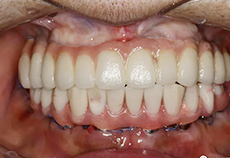

治疗完成

种植牙

DENTAL IMPLANT